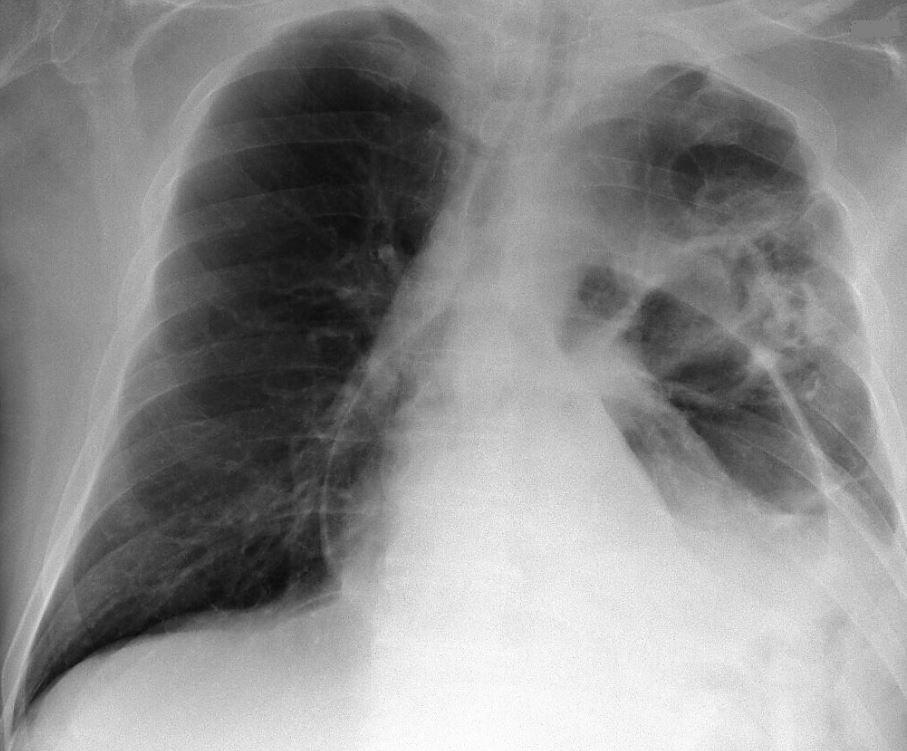

Een 65-jarige man komt naar de Spoedeisende Hulp met ‘een luchtig gevoel’ in de linker thoraxhelft. De voorgeschiedenis vermeldt een cerebraal en lymfogeen gemetastaseerd bronchuscarcinoom, waarvoor hij palliatieve chemotherapie krijgt.

Wat is uw diagnose?